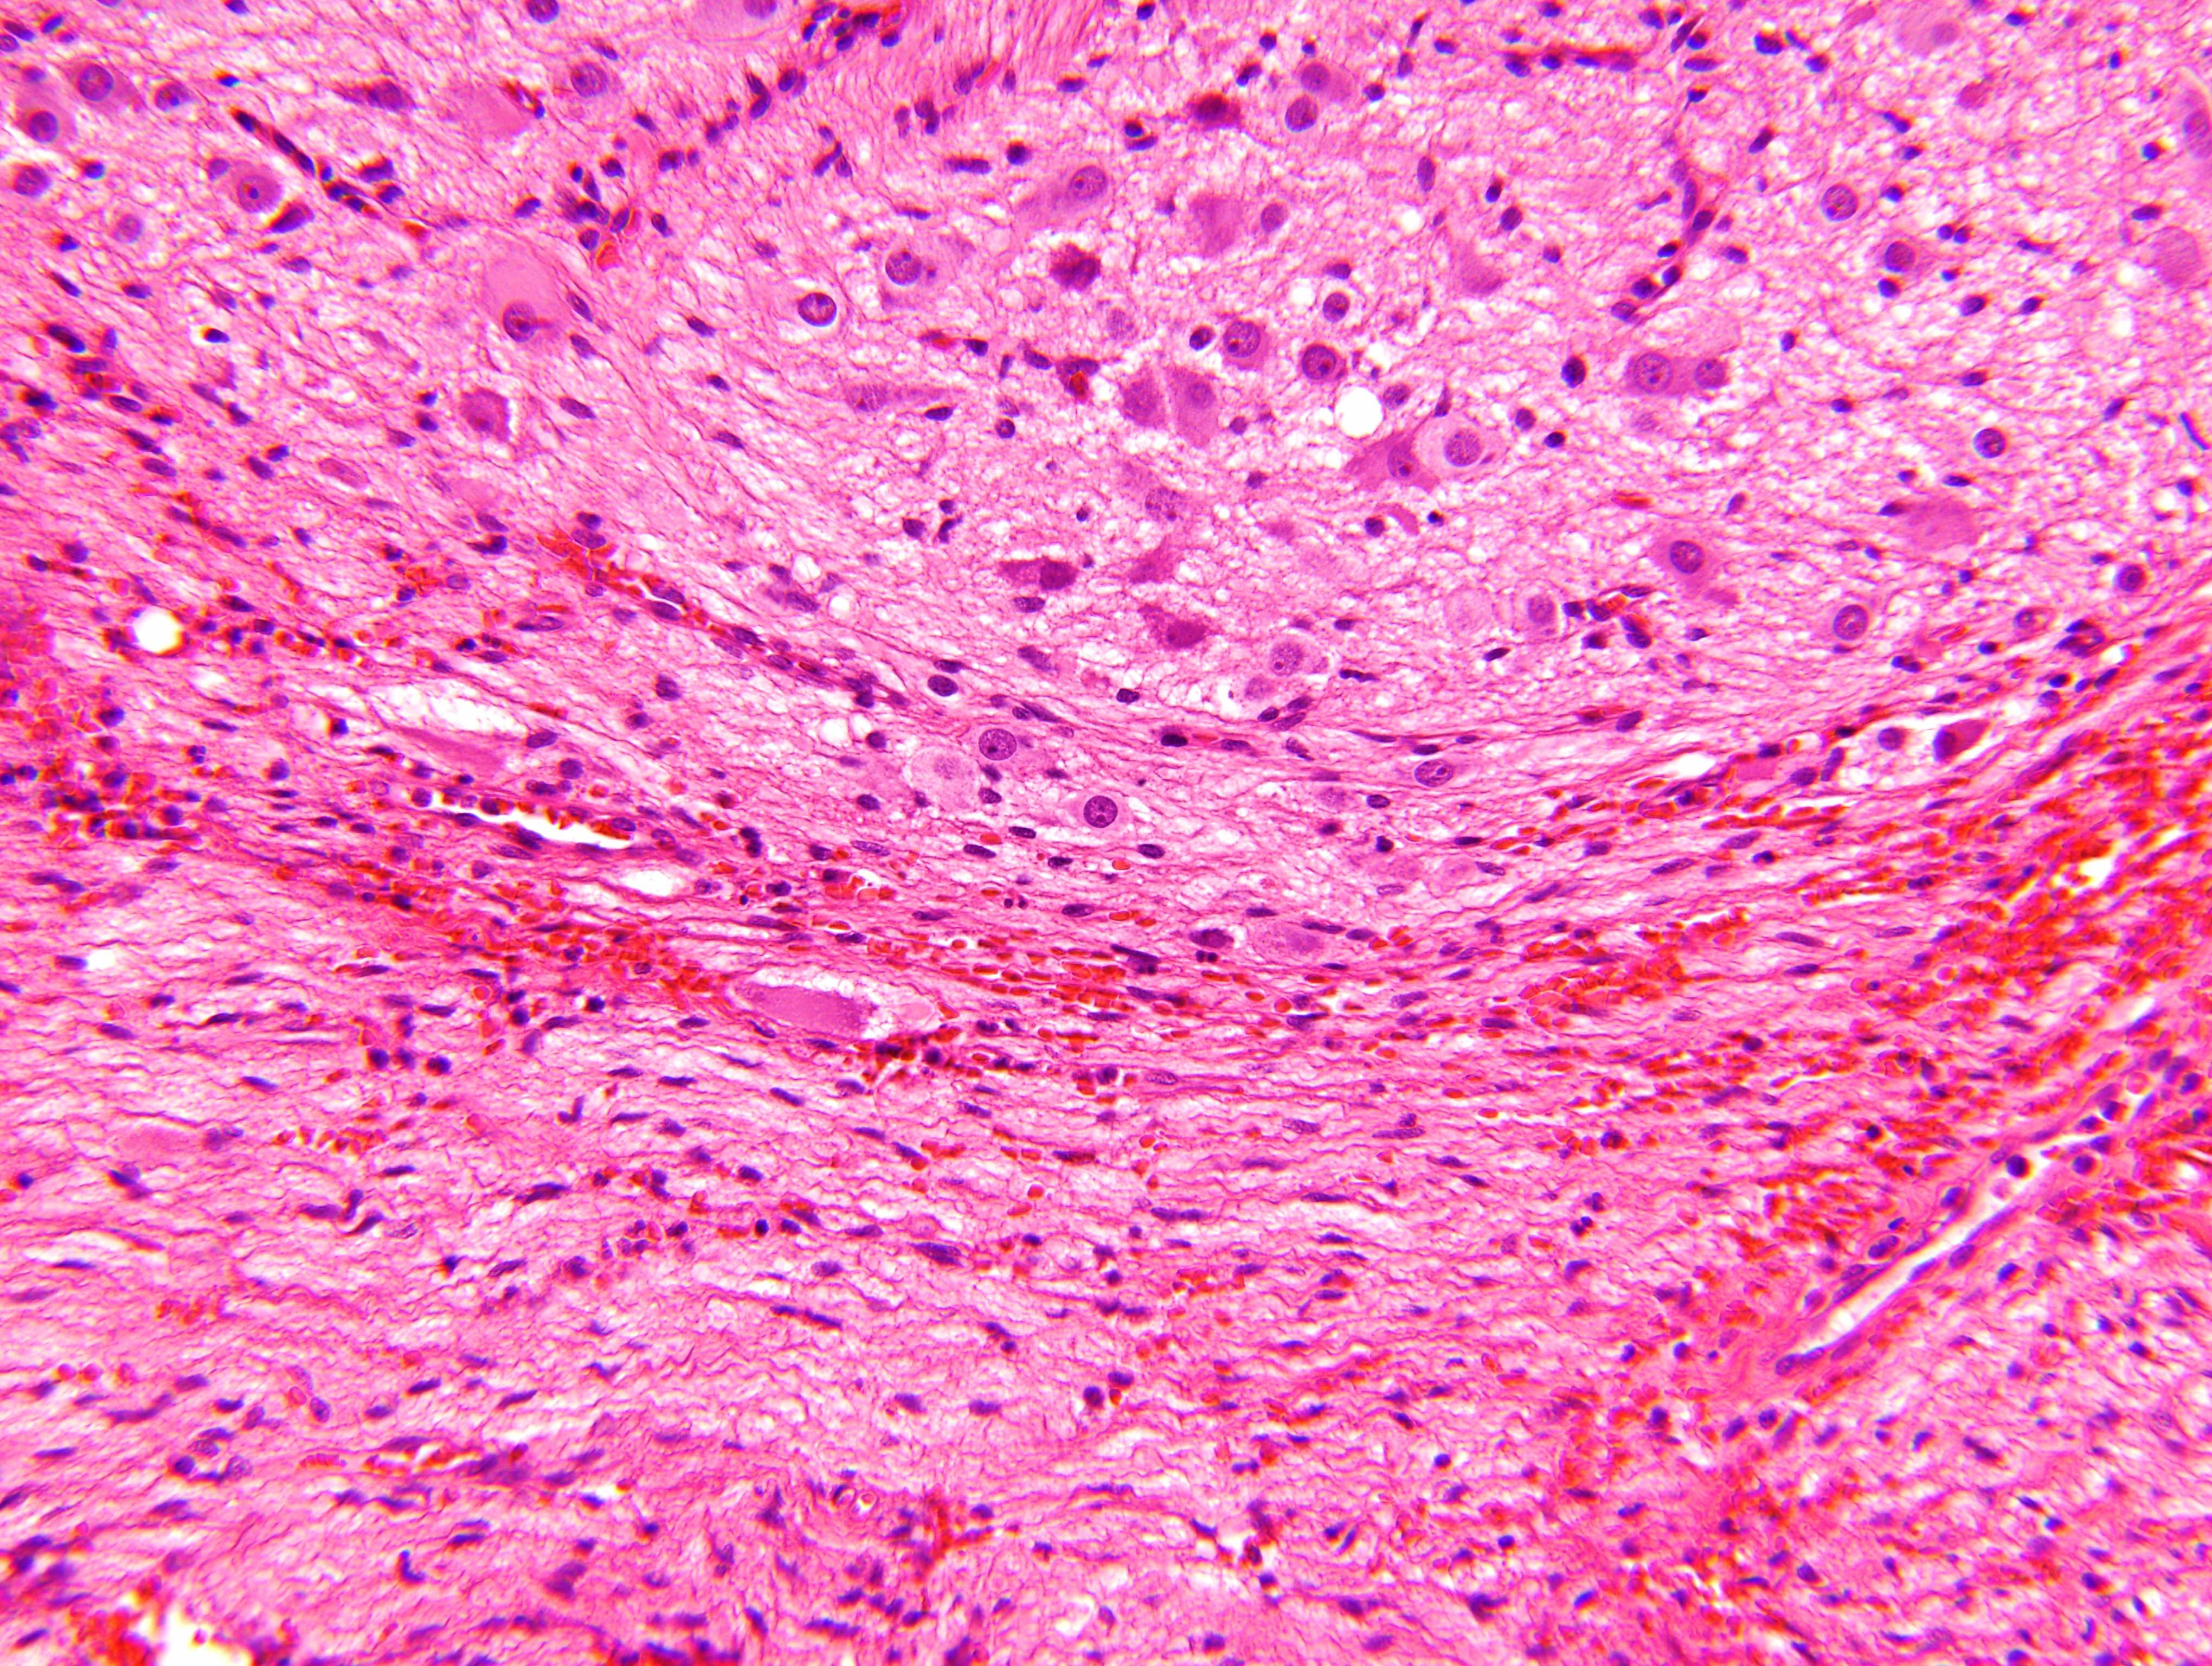

Microscopic (histologic) description

- Architecture: lobular, diffuse / solid, organoid

- Neuroblasts

- Homer Wright pseudorosettes = circular, ovoid, angular zones of pale staining neuritic cell processes surrounded by tumor cell nuclei; may rarely palisade

- Minimal cytoplasm, may have cytoplasmic tail

- Round to ovoid nuclei with stippled salt and pepper chromatin, inconspicuous nucleoli

- Ganglion cells

- Abundant granular eosinophilic cytoplasm (Nissl substance = rough endoplasmic reticulum)

- Distinct cell borders

- Nuclear enlargement, eccentric nuclei, prominent nucleoli

- May see neuromelanin pigment (brown, finely granular; rarely present), cystic degeneration, hemorrhage, dystrophic calcification

Microscopic (histologic) images

Contributed by Carmen Perrino, M.D. and Debra L. Zynger, M.D.

Intermixed type

Nodular type